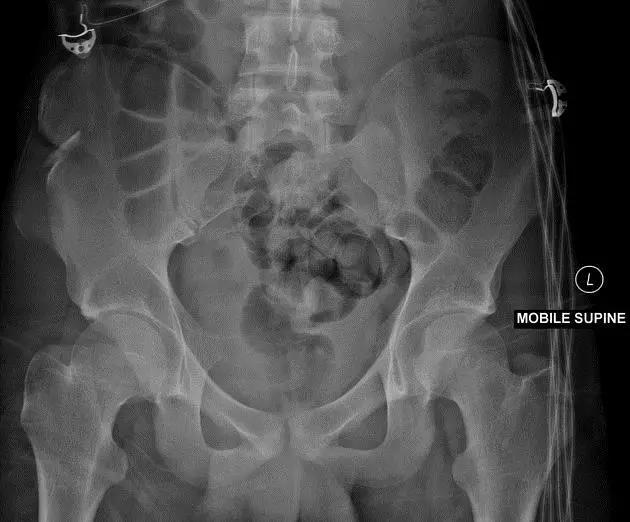

2. Malgaigne 骨折 (bucket handle 骨折,即桶柄骨折)

不稳定性骨盆骨折伴有前方和后方的骨折线累及髋关节。

(来源:radiopaedia)